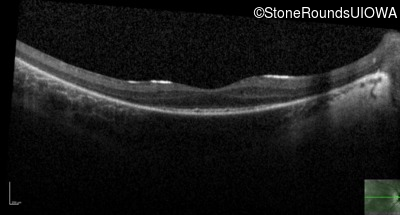

Optical Coherence Tomography - Right - 20/60

Exemplar / OCT Stack